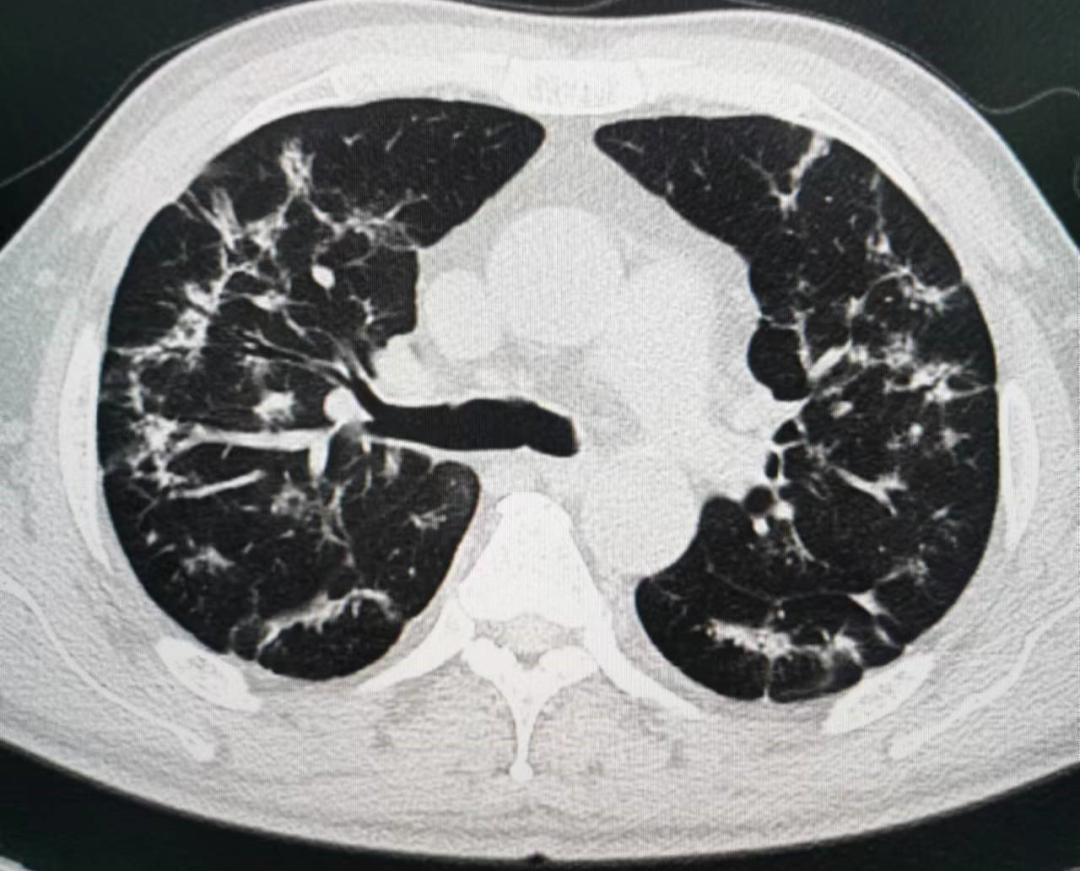

六、重症期征象:肺部病变一般在发病后14天左右达到高峰,少部分病例急剧进展,病变累及双侧全肺,呈“大白肺”(肺部受累面积超过70%)其内可见空气支气管征,双侧胸腔可有少量胸腔积液,临床纳入危重症管理。

病理学基础:提示肺泡腔有大量纤维素性渗出。